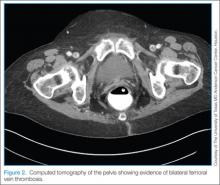

The patient visited the emergency room several times during the following months because of intermittent exacerbations of her lower extremity pain, swelling, and occasional paresthesias. About 6 months after initial presentation, repeat MRI again showed increased size of the mass (13.5×13.5 cm axial, 28 cm craniocaudal). There was also increased displacement of the adjacent neurovascular structures but no evidence of deep vein thrombosis. Because of concerns about the increased symptomatology of her thigh mass and possible sampling error of the previous biopsies, an elective cesarean section was performed at 35 weeks gestation. One week later, after clearance by her obstetrician, we proceeded with open biopsy of the mass in prone position. Initial sampling was negative for malignancy on frozen section; then, we expressed 1.75 L of brown fluid and solidified blood products, irrigated copiously, and placed a surgical drain. The permanent histologic specimens were again consistent with hematoma, and microbial cultures were negative. A week later, the patient accidentally removed her drain, and she presented with a fever (101°F) on postoperative day (POD) 15. Computed tomography showed reaccumulation of fluid; duplex ultrasound was negative. She was placed on cephalexin and underwent ultrasound-guided replacement of the drain with removal of an additional 750 mL fluid on POD 20. She drained an additional 150 to 200 mL/d for 1 month, with marked improvement in her leg swelling and knee range of motion. The drainage decreased during the next 3 weeks, and the drain was removed on POD 75.